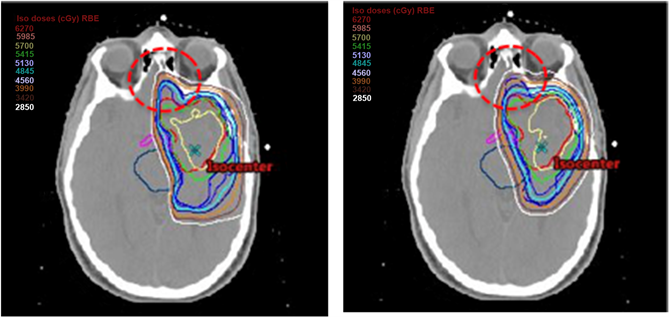

Basically, overestimating the dose to target and underestimating the maximum dose to critical organs by the TPS clinically poses a critical problem. In this analysis, the TPS overestimated 400 - 500 cGy (RBE) for the minimum dose to the CTV in the SFO and MFO IMPT plans. Dose difference of the TPS and the FDC for D95 in plan L was 4.8%, which is considered somewhat large. As shown in the red dashed circle region in Figure 6, we found considerable dose deterioration in front of the CTV in FDC for plan L. Since this region consisted of bone, cavity, and soft tissue and therefore had large heterogeneities, beams of 340˚ and 20˚ affected this difference between the TPS algorithm and the FDC.

Figure 6. Comparison of isodose distributions obtained by the TPS (left) and the FDC (right) for plan L.